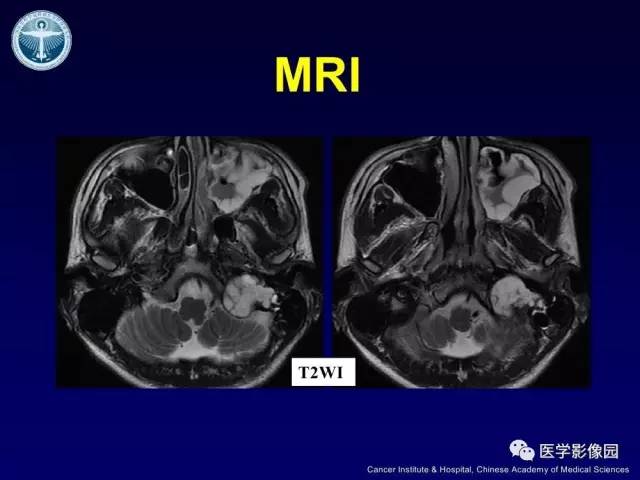

【病例】左侧颈静脉孔区脊索瘤1例MR影像表现